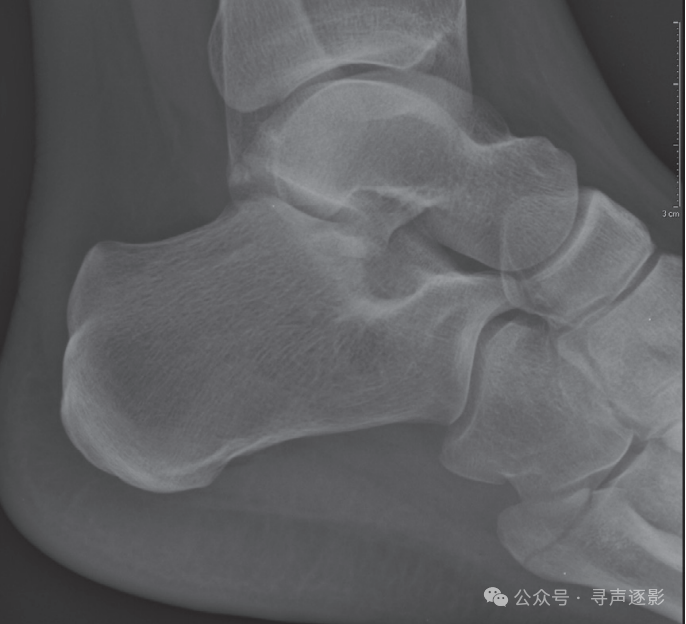

左图:外踝横形骨折。右图:内踝横形骨折;腓骨远端及外踝斜形与横形骨折;距骨外侧半脱位。

左图:胫骨与腓骨多处骨折。右图:注意胫腓关节间隙明显增宽,提示骨间膜断裂。距骨外侧突可见小碎骨片(箭头所示),提示韧带损伤。

在实际工作中,必须将前后位片与侧位片视为一组,一并评估。该患者的前后位片显示外踝横形骨折及距骨外侧半脱位;侧位片则清晰呈现腓骨骨折的全长及移位程度,并可同时评估后踝、距骨及跟骨的情况。